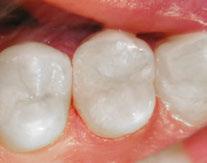

Summary

An alternative approach of single visit regenerative endodontics was employed utilizing the GentleWave system to facilitate disinfection and blood clot formation. After the IV was placed, local anesthesia was administered using 3% mepivacaine. No vasoconstrictor was used so as not to inhibit blood flow to the tooth. After isolating with a rubber dam, the tooth was accessed. A necrotic pulp was noted. No endodontic files were used for instrumentation. Flowable dam material (EndoSequence® , Brasseler USA) was used to build a platform and create a seal for the GentleWave CleanFlow™ procedure instrument (Sonendo). The full GentleWave cycle was run using NaOCl and EDTA as irrigants with a final water flush. Once the platform was removed, bleeding was immediately noted in the canal (Figure 4). A microsuction tip was used to control the bleeding to below the level of the CEJ. A piece of collagen tape (HeliCote® Collagen Dressing by Integra Miltex) was placed over the blood clot (Figure 5). Bioceramic putty (EndoSequence BC RRM Fast Set Putty) was placed on top of the collagen tape (Figures 6 and 7). The chamber was then etched and bonded and restored using Luxacore build up material (LuxaCore Z Dual Cure) and light-cured resin composite (Clearfil Majesty™ Composite, Kuraray) (Figures 8 and 9).

Figure 5 (left): Collagen tape was placed directly over the blood clot. Figure 6 (center left): Bioceramic putty was placed directly over the collagen tape. Figure 7 (center right): Periapical radiograph showing the placement of the bioceramic putty in the canal. Figure 8 (right): Restored access